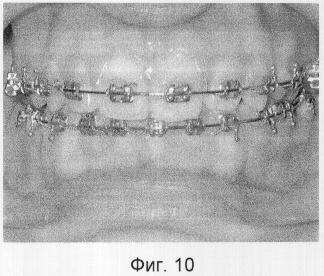

На фигурах 1-3 изображены схемы выполнения способа; на фигурах 4-10 – фотографии, иллюстрирующие клинические примеры.

Под местным обезболиванием проведена остеотомия альвеолярного края нижней челюсти от первого премоляра до первого премоляра противоположной стороны. Установлена стальная дуга 0,17×0,25 (паз брекета – 0,18) с реверсионным изгибом. Спустя 8 дней начаты активации дуги, направленные на вестибулярное отклонение корней нижних резцов. Через 3 месяца после операции достигнуто нейтральное соотношение челюстей, множественные окклюзионные контакты (фиг.10).